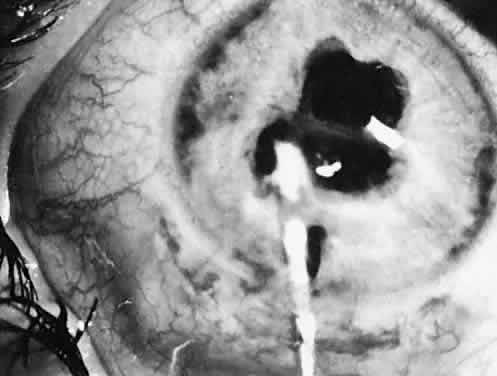

Not all cataracts require surgical treatment. Eyes with punctate or small anterior polar cataracts and others with partial opacification of the lens, such as posterior lenticonus, which only slightly interferes with the refraction of light, are best followed and not surgically treated (Fig. 1). In some cases, it is difficult to determine whether the presence of a partial cataract is responsible for a decrease in visual acuity or whether the refractive error or optical distortion produced by the cataract has produced a mild, reversible form of deprivation amblyopia. In these situations, correction of the refractive error and a trial of occlusion therapy should be attempted. If the visual acuity improves, it may be deduced that amblyopia was responsible for the loss of visual acuity and that the optical distortion produced by the partial cataract is not yet surgically significant.

Fig. 1. Cataracts that do not require surgical treatment. A. Anterior polar cataract. Visual acuity is 20/25. B. Partial punctate or cerulean cataract. Visual acuity is 20/30.

Type and Location

Usually, anterior polar cataracts are visually insignificant and allow normal visual development (see Fig. 1). However, some affect vision, and all require careful monitoring.7 Centrally located cataracts that are on or near the posterior lens capsule have a greater effect on the refraction of light and visual acuity (Fig. 2). Nuclear cataracts associated with metabolic disorders or prenatal infections produce double refracting systems that cause optical distortion and significantly decrease visual acuity (Fig. 3).